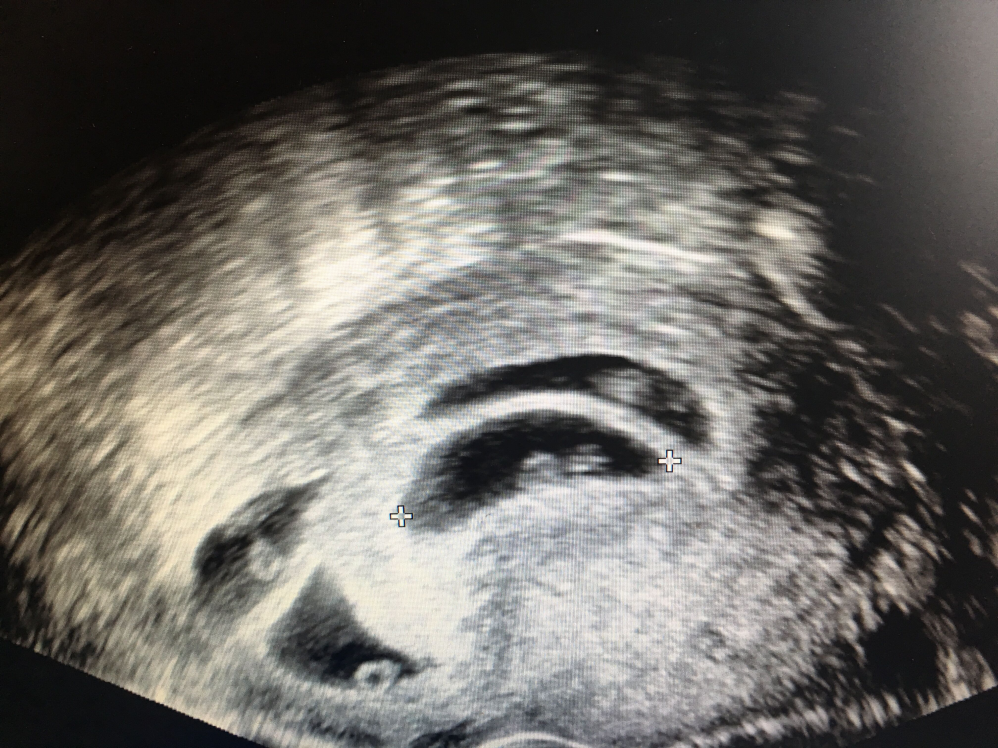

一个B超切面已经放不下6个胚胎

这是来我院生殖医学中心减胎的一位妈妈,因为滥用促排卵药物,而且没有正规监测,当发现怀孕的时候已经是6胎“济济一堂”,夫妇俩一辆愁容到我院生殖中心寻求帮助。减胎虽有风险,但是若不减胎势必全军覆没,这个妈妈减胎后是happy ending的结局,成功分娩一对健康的龙凤胎。